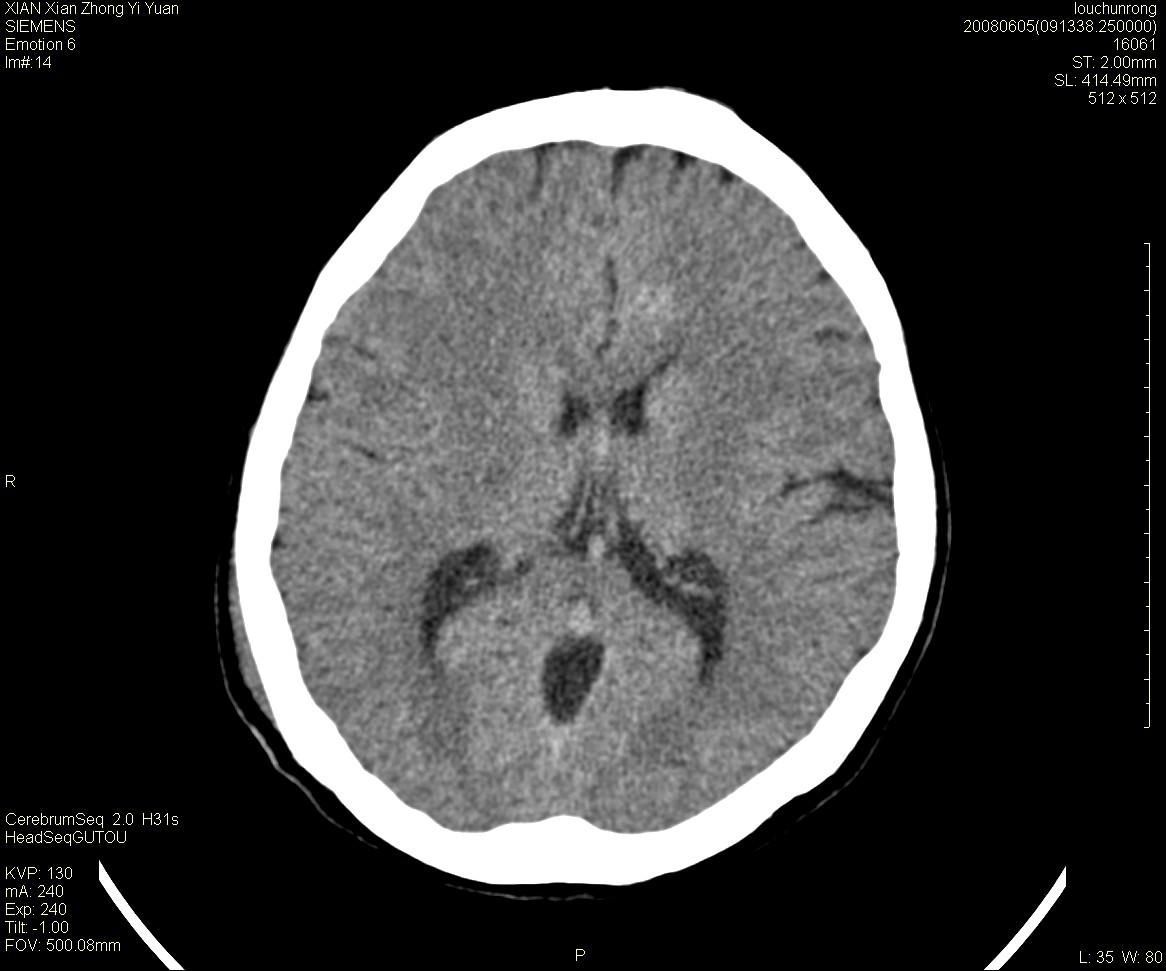

标题: CT13860:F52Y,,头外伤致头晕半天,以前无不适。 [打印本页]

标题: CT13860:F52Y,,头外伤致头晕半天,以前无不适。

层厚2mm。

大家看左额叶大脑镰旁高密度影

大脑大静脉池内的密度不均,双侧脑室增宽,我看右异常这块。战友们看看